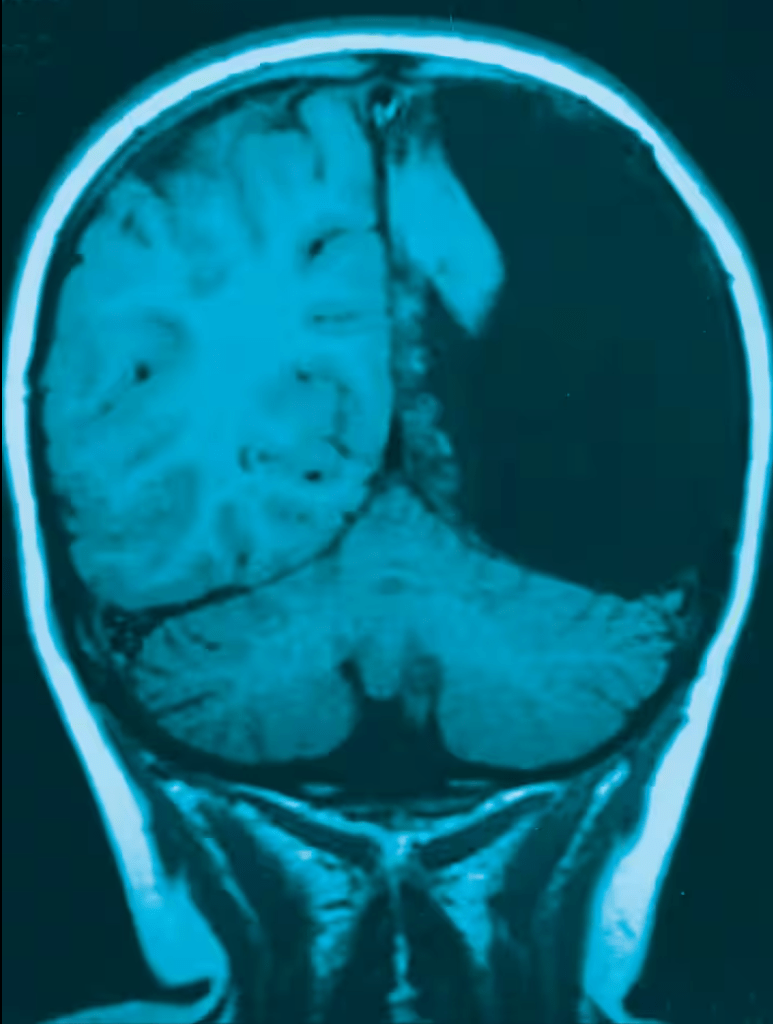

Rätselhaft: Einer Siebenjährigen aus den Niederlanden musste im Alter von drei Jahren das halbe Gehirn entfernt werden. Trotzdem spricht das Mädchen heute fliessend zwei Sprachen.

Selbst mit nur einer Hirnhälfte lässt es sich bisweilen normal leben. Das belegt die Fallstudie «Ein halbes Gehirn» von Johannes Borgstein und Caroline Grootendorst 2002 im Fachblatt «The Lancet». Die Mediziner vom Unispital Rotterdam zeigen darin die Magnetresonanztomografie-Aufnahme des Schädels einer Siebenjährigen.

Ihre linke Hirnhälfte fehlt. Chirurgen hatten sie dem Mädchen wegen einer chronischen Gehirnentzündung mit schweren epileptischen Anfällen entfernt, als es drei Jahre alt war. Welche Folgen hatte diese Hemisphärektomie? Es ist kaum zu glauben: So gut wie keine.

Vier Jahre nach der dramatischen Hirnoperation spricht das Mädchen fliessend zwei Sprachen, entwickelt sich bestens und lebt ein normales Leben. Die durch die Grunderkrankung verursachte halbseitige Lähmung ist verschwunden. Zurück blieb einzig eine leichte Verkrampfung in einem Arm und einem Bein.